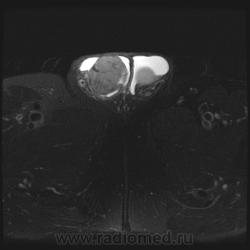

"Мужчина, 60 лет. Около 3 месяцев назад появился дискомфорт в области мошонки, увеличение правого яичка."

Считаю, что семинома - не самый вероятный вариант, т.к. структура опухоли достаточно неоднородная, есть распространение на придаток и границы четкие.

Могу предположить, неоплазию правого яичка.

Я в заключении вынес на первый ряд карциному яичка.